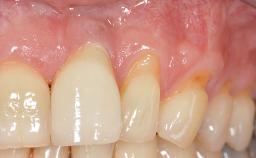

It is sometimes necessary to remove and replace compromised implants. This case is a clear example of the need for multiple steps to achieve an optimal therapeutic result for patients with non-salvageable implants. It illustrates how the lost soft and hard tissues were rebuilt in a sequence that improved the healing of the hard tissues and assured their long-term stability. The 35-year-old healthy patient presented with clinical attachment loss on the proximal and lingual surfaces of the natural dentition. Some gingival recession was present on natural teeth, particularly in the posterior sextants (S1, S3, S4, and S6).